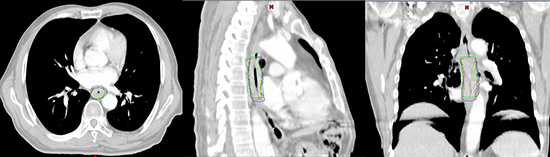

In all cases, the GTV and/or IGTV contouring were completed by the same clinician, with more than 5 years of experience performing target volume delineation, using the mediastinal window setting. The GTV and/or IGTV for each patient were delineated as follows: (1) the GTV3D and GTV4D50 were delineated on CE-3DCT and CE-4DCT50 images (the end expiration phase of CE-4DCT), respectively; (2) the IGTVMIP and IGTVCBCT were delineated separately on the CE-4DCTMIP (the maximum intensity projection of CE-4DCT) and CE-CBCT datasets, respectively; and (3) the GTVs on each of the 10 respiratory phases of the CE-4DCT images were delineated and combined to produce IGTV10 (Figure 1).

Figure 1: Gross target volume (GTV) or internal GTV (IGTV) formation in one patient: (green), GTV3D; (red), GTV4D50; (purple) IGTVMIP; (blue) IGTV10; (yellow) IGTVCBCT. The figures are the axial, sagittal and coronal view of one patient exhibiting the GTV or IGTVs.